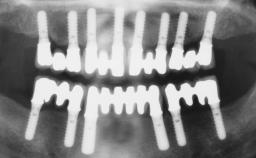

Immediate Loading of Six Implants in the Maxilla and Final Restoration with a Full-Arch Gold/Ceramic FDP Involving the Concept of Tilted Implants

A 61-year-old male patient with a failing fixed maxillary rehabilitation and a fixed mandibular rehabilitation requested a new fixed maxillary rehabilitation. The patient was wearing a temporary metal-reinforced maxillary bridge inserted two years before the consultation. He reported that his previous dentist did not want to insert a definitive framework because he considered the residual teeth to have a negative prognosis. The patient reported a history of recurrent caries and endodontic complications as the main reason for the previous extractions. The anamnesis was negative for periodontal disease and bruxism. The patient’s chief compliant was the mobility of his maxillary prosthesis, which needed to be re-cemented frequently, and discomfort during chewing.Moreover, the patient was not satisfied with the esthetic appearance of his maxillary teeth, which he found too long. The patient asked for a stable and comfortable fixed maxillary rehabilitation and firmly rejected any removable solution.

# of Implants 6

Type of Implants One-Piece|Reduced-Diameter

Prosthesis Type FDP